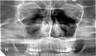

ПАНОРАМНАЯ РЕНТГЕНОГРАФИЯ (рис.1) – методика, позволяющая получить на одной пленке развернутое (несколько увеличенное) изображение одной из челюстей.

Рис.1. Панорамная рентгенограмма верхней челюсти

Для получения изображения применяется рентгеновский аппарат со специальной острофокусной рентгеновской трубкой. Анод рентгеновской трубки во время съемки вводится в полость рта пациента. При съемке верхнего зубного ряда фокус трубки располагают над языком на уровне пятых зубов, для съемки нижнего ряда – в области уздечки под языком. Рентгеновская пленка форматом 18х24 см помещается в гибкую полиэтиленовую кассету с усиливающими экранами высокой разрешающей способности. Во время съемки больной прижимает руками кассету к коже вокруг исследуемой области лица. Если кассета фиксирована неплотно, изображение структуры костей получается нечетким.

Поскольку фокус рентгеновской трубки максимально приближен к объекту исследования, а пленка находится на некотором расстоянии от зубов, обусловленном толщиной мягких тканей, изображение получается увеличенным почти в два раза. Благодаря этому обстоятельству на панорамных снимках различимы мелкие детали, плохо видимые на обычных рентгенограммах.

На панорамных снимках верхней челюсти получается также изображение верхнечелюстных пазух, полости носа, бугров верхней челюсти и скуловых костей. На нижней панорамной рентгенограмме хорошо видны нижнечелюстной канал и основание нижнечелюстной кости. На боковом панорамном снимке одновременно отображаются зубы верхнего и нижнего ряда каждой половины челюсти.

На основании панорамных снимков диагностируют кариес и его осложнения, воспалительные процессы, кисты, новообразования и травматические повреждения челюстей. Однако для оценки степени резорбции межальвеолярных гребней этот метод не пригоден.

Недостатком панорамной рентгенографии является также невозможность контролировать положение во рту аппликатора рентгеновской трубки.

Существенному облучению при этом методе исследования подвергается слизистая оболочка полости рта, поэтому панорамную рентгенографию рекомендуется использовать только при показаниях и не более 1-2 раз в год для каждого пациента. Дополнительная защита при этом виде рентгенографии малоэффективна, т.к. облучению подвергаются органы полости рта, находящиеся вне защитной зоны.

Следует иметь ввиду, что данная методика, в связи с появлением в последние годы более современных способов исследования, используется редко.